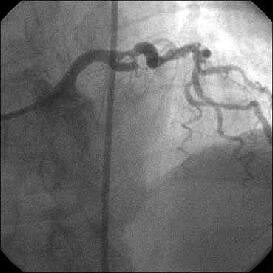

�Ǘ��72�Ώ����Brisk factor��HT, HL, DM�ł��B

��2�T�ԑO�̔��ǂƎv����Recent MI�ł��BLAD#7: total��Tristar3.0�~18?�����

�܂����B

����LCx ostium: 75%�ł��B������PCI���悤�Ǝv���̂ł����A�ǂ̂悤��strategy

���l������ł��傤���H

���Ȃ݂ɓ��@�ł�DCA�g�p�o���҂͂��܂���B

DCA�ł���l��A��Ă���A�Ƃ����I�������܂߂Č䏕��������K���ł��B

�X�������肢���܂��B

|

|

|

|

|

����������������������������������������������������������������������������